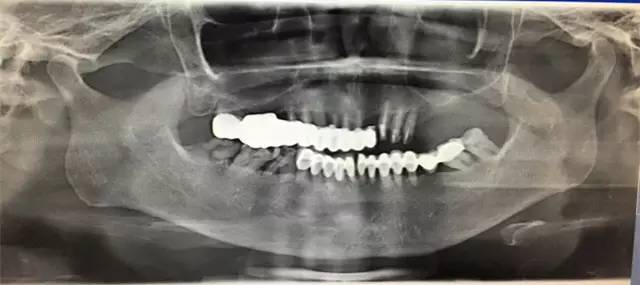

而美容冠则要将健康牙齿磨小,然后套上整齐的“假牙套”,如果用X光片查看,会发现牙根部位依旧凌乱。